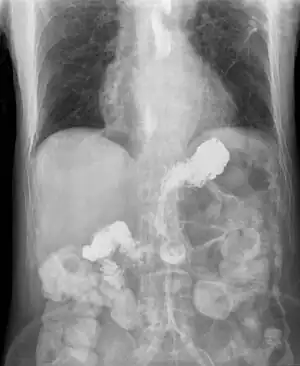

| X-ray showing radiocontrast from the stomach (white material below diaphragm) entering the esophagus (three vertical collections of white material in the mid-line of the chest) due to severe reflux | |